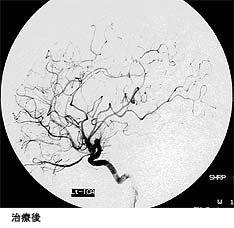

動静脈奇形部分に集中的に放射線を照射する治療法です。小型の病変が治療対象となります。サイバーナイフ治療の前後のMRIと血管撮影の画像を下に提示します。

(画像は、日本赤十字社医療センター 脳神経外科 野村竜太郎先生のご好意による)